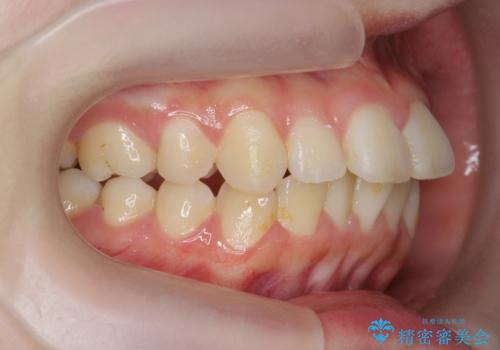

- 前歯の角度 奥歯の噛み合わせの改善をするために、矯正治療を希望され来院されました。

右側奥歯は上顎が相対的に前方に位置し(上顎前突)、そのため前歯の角度も突き出たようになり出っ歯のように見える状態でした。

マイクロインプラントを用いて、上顎奥歯を後方に移動させることで噛み合わせ・前歯の角度を改善していきます。

少し時間はかかりましたが、しっかりと綺麗な歯並びに仕上げることができ、大変喜んでいただくことができました。